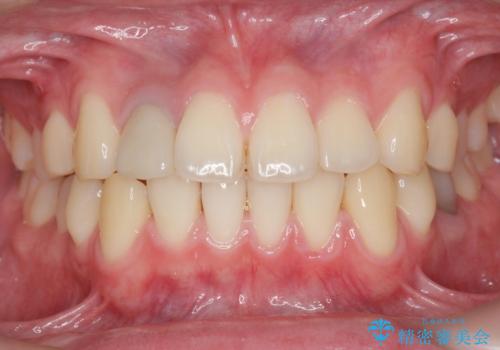

土台を白いファイバーコアにやりかえたのち、土台の色を透過させないジルコニアフレームを用いたセラミッククラウンによる治療を行いました。

自然な仕上がりにご満足頂けました。

治療終了時には「修正や仮付けをしてもらえて納得のいく治療を受けられました。この病院にして良かったです!」とおっしゃって下さいました。

クラウンの種類:オールセラミッククラウン スペシャル